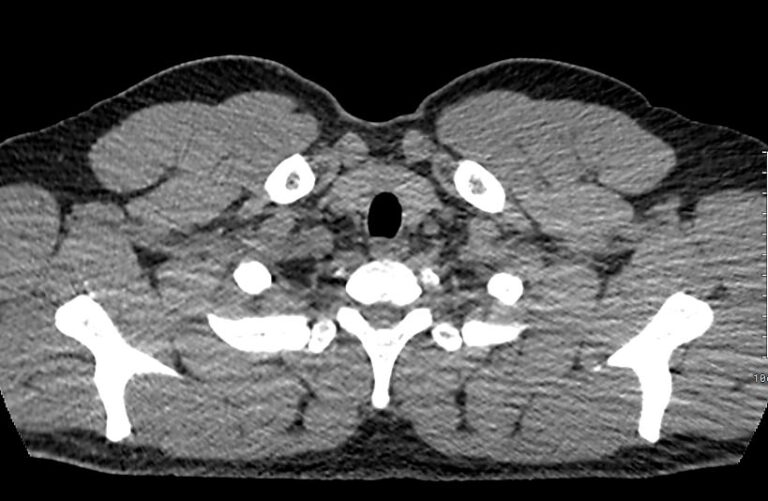

Наиболее информативным современным способом визуализации лимфоузлов является мультиспиральная компьютерная томография. Методика предусматривает послойное сканирование исследуемой области при помощи проникающего действия рентгеновских лучей.

В нашей клинике КТ лимфатических узлов средостения проводится на новейших мультиспиральных томографах экспертного уровня, которые производят тончайшие срезы исследуемой зоны толщиной от 0,5 мм и позволяют визуализировать лимфоузлы и прилегающие мягкие ткани с высокой детализацией. Увеличенное количество высокочувствительных детекторов аппарата обеспечивает высокую разрешающую способность и четкость изображений, при этом позволяет выполнить исследование в течение нескольких секунд с минимальной дозой облучения.

Методика КТ позволяет оценить структуру лимфатических узлов, обнаружить неоднородность, гиперплазию, деформацию их контуров.

Информация, полученная при помощи мультиспиральной компьютерной томографии, дает возможность визуализировать размеры лимфоузлов, их точную локализацию, взаимодействие с близлежащими органами и окружающими тканями, образование пакетов и конгломератов лимфоузлов, выявить инфильтрацию прилегающих анатомических областей.